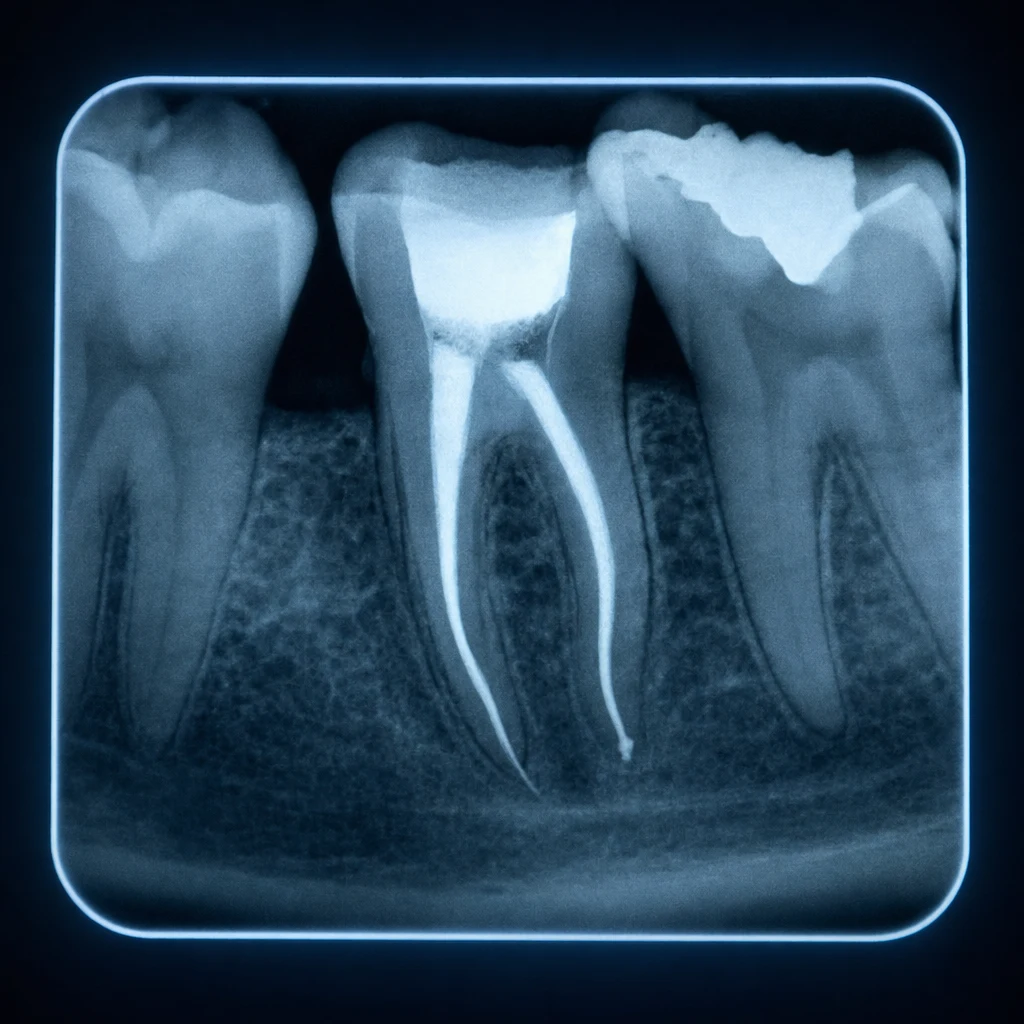

신경관은 매우 가늘고 분지가 복잡합니다. 일부 부위에 감염이 남아있으면 시간이 지나면서 다시 활성화됩니다. CBCT 또는 미세현미경 검사로 확인 가능합니다.

2. 치근 균열 (Vertical Root Fracture)

신경 제거 후 치아는 영양 공급이 끊겨 점차 단단함이 줄어듭니다. 보철을 미루면 강한 저작력에 의해 치근에 미세 균열이 생길 수 있습니다. 균열은 일반 X-ray에 잘 보이지 않아 정밀 검사가 필요합니다.

X-ray에 치근단 부위 검은 음영(치근단 병변)이 새로 보이면 만성 잔존 감염이 진행 중인 상태입니다. 통증이 거의 없어도 재근관치료 또는 발치 결정이 필요합니다.